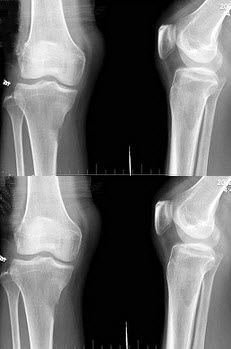

89、单项选择题

男,根据其正常骨盆影像图像,判断其最可能的年龄()

A.2岁左右

B.8岁左右

C.6岁左右

D.12岁左右

E.10岁左右